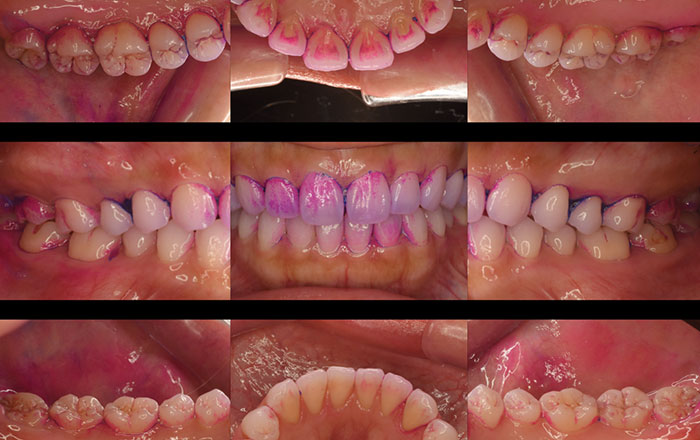

必要に応じて、染め出しを行ってばい菌を見えるようにし、歯みがきの仕方を確認します。

2)染め出し

歯に付着しているバイ菌は、通常だと目で見ることができません。

そのため、磨き残しがないか、染め出し液でバイ菌がどこに付着しているのか、分かるようにして確認します。

3)口腔内写真撮影

カメラで、お口の中の写真撮影をします。

写真撮影を行うことで、歯の裏側など普段自分では見えないところまで細かく見ることができます。

(場合によっては、染め出し前の口腔内写真撮影も行います)